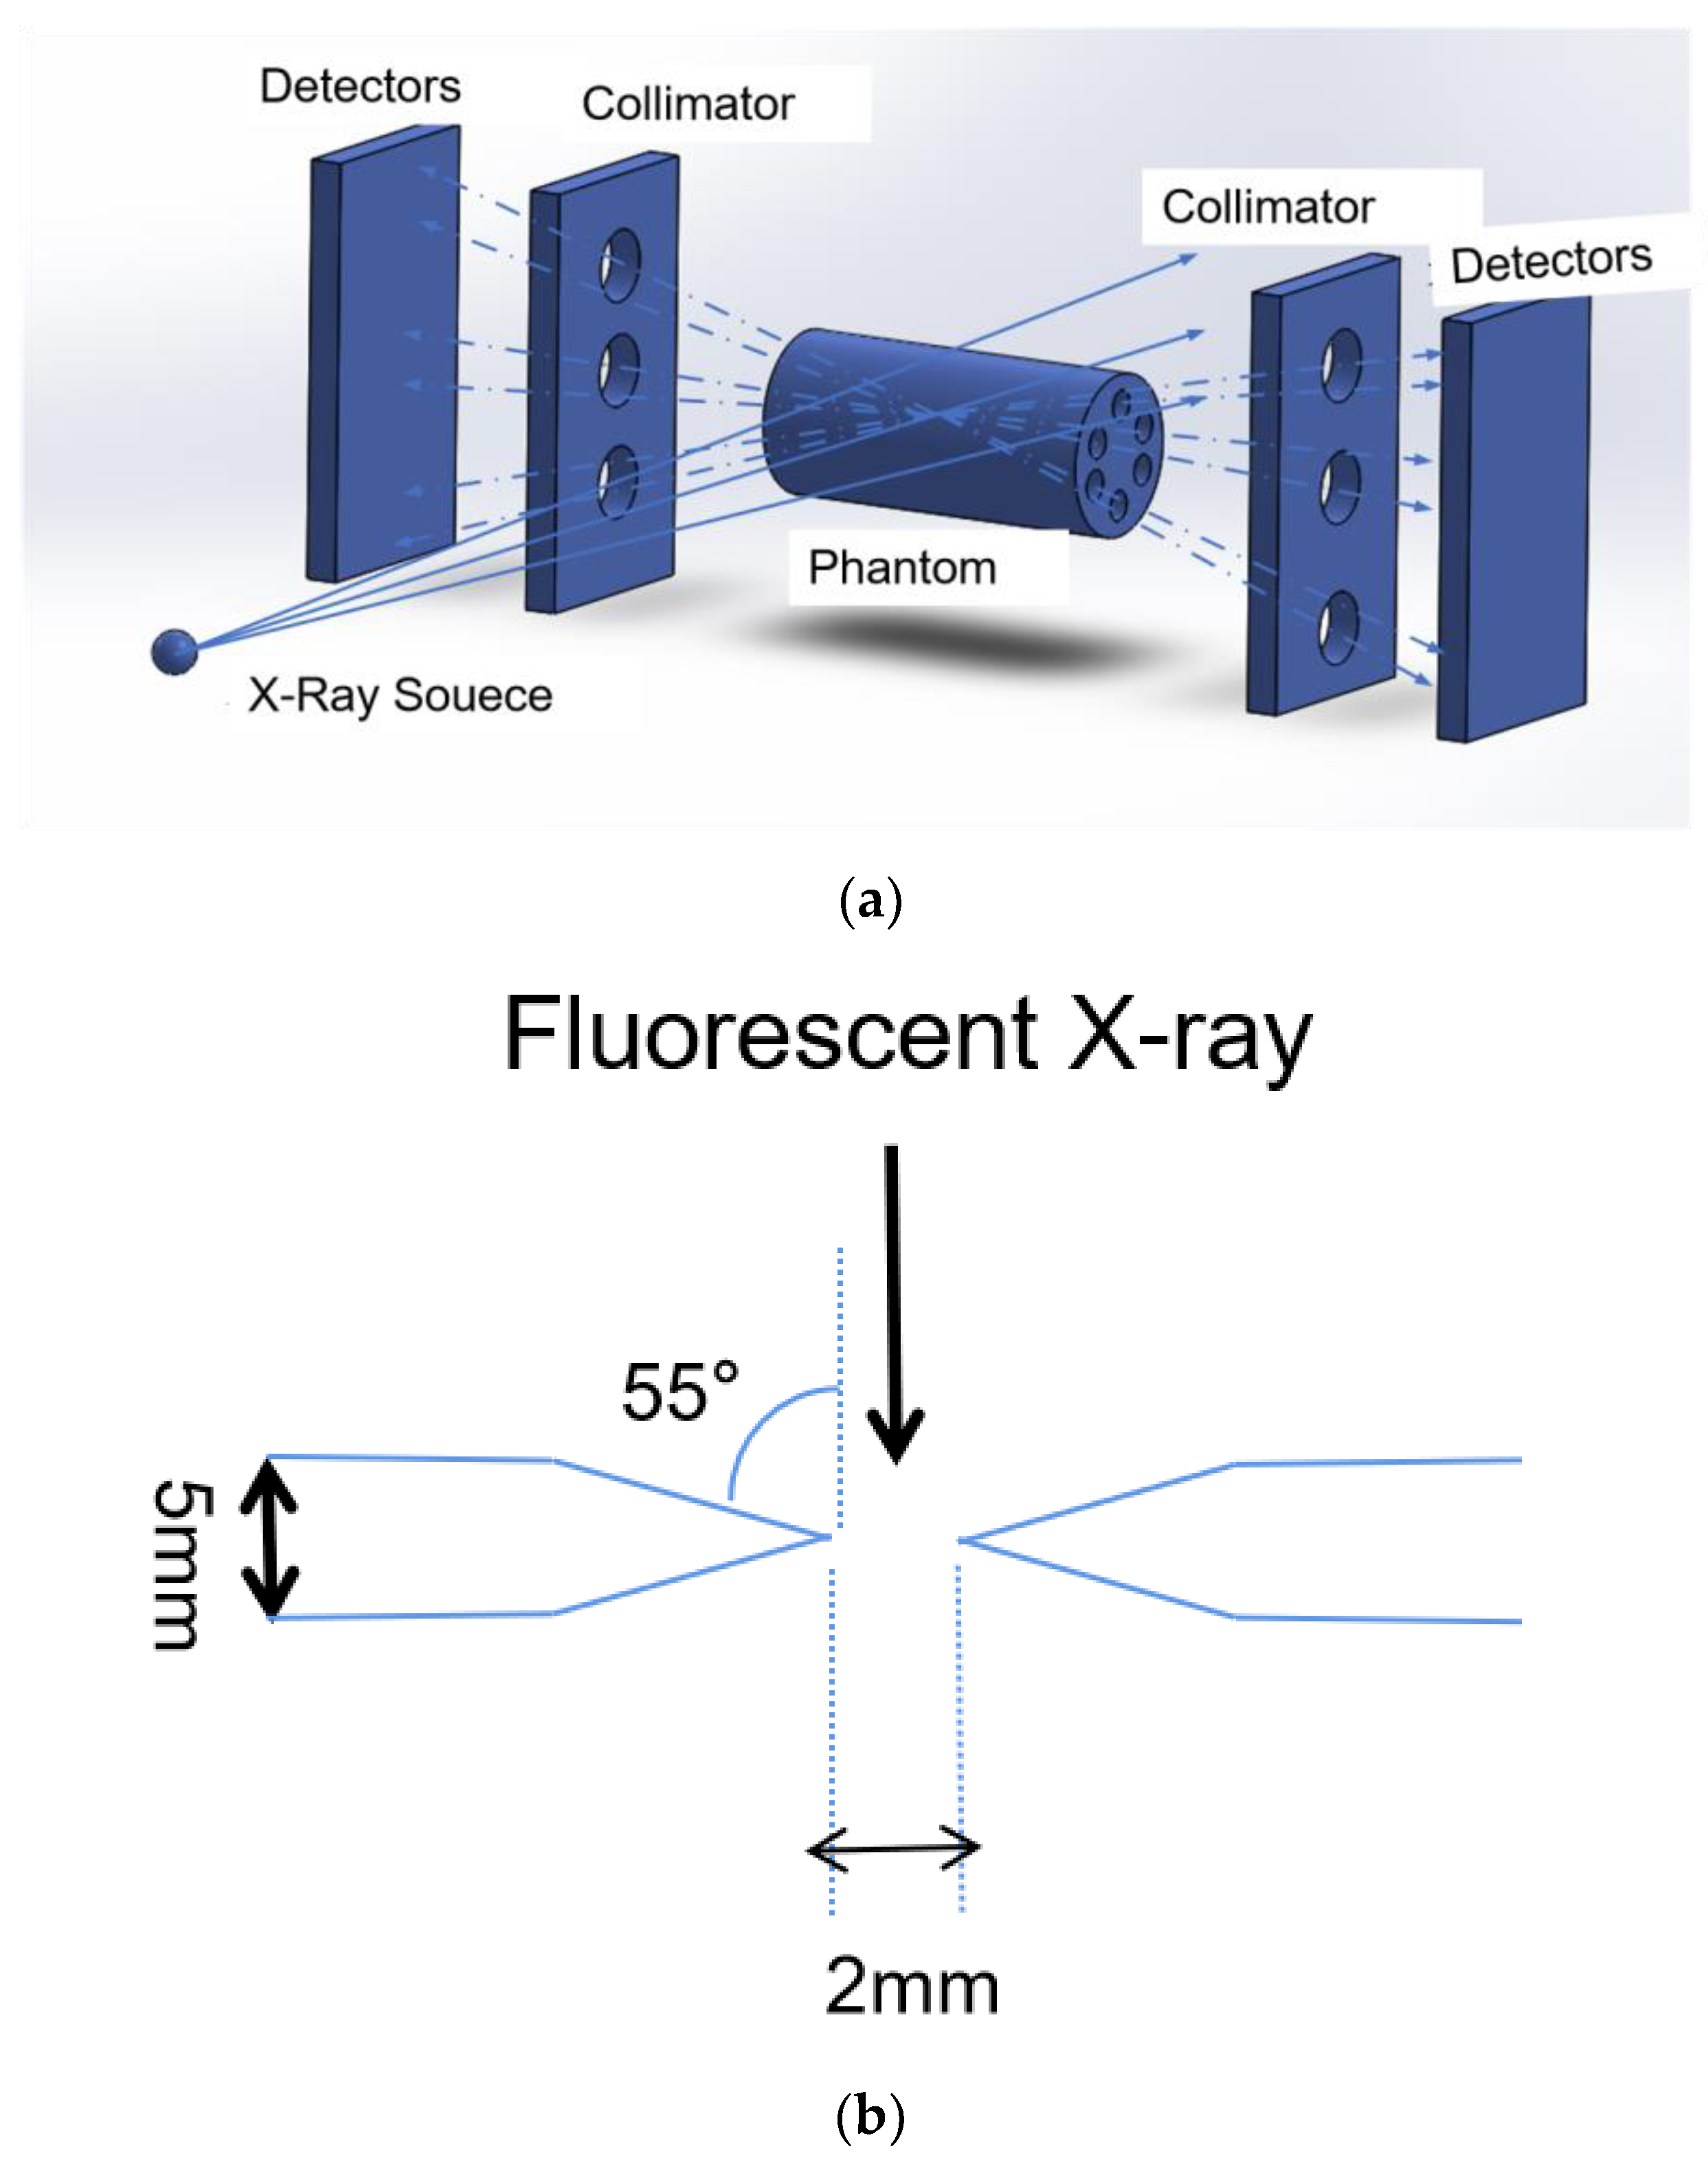

2.1. XFCT Theory

2.3. Datasets

2.4. Network Architecture